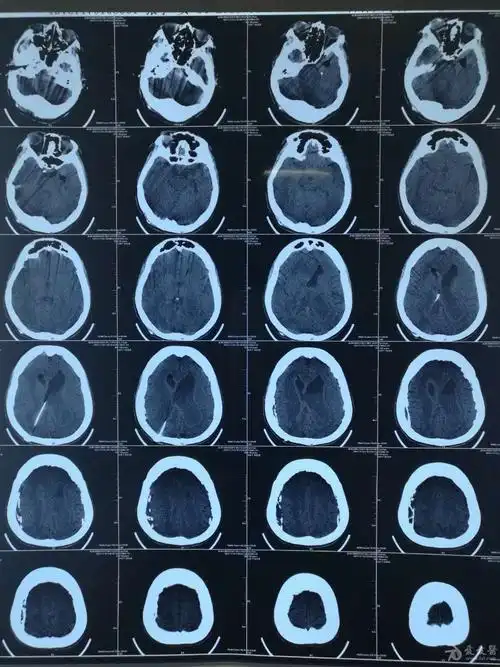

罕见脑积水病例